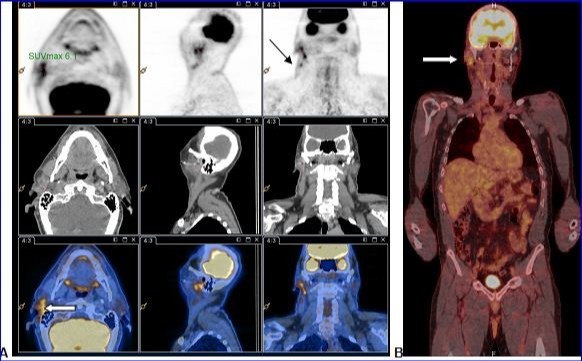

PET-CT with 18F-FDG injection of iodinated contrast post surgery showed an intense and diffuse hyper metabolism at the surgical site in the right parotid and discreetly moderated hypermetabolic lymph nodes in the ipsilateral lymph nodes areas II and III. No morphological or metabolic argument for tumor was demonstrated (either primary or secondary) on the whole-body (Figure 2).

Figure 2.A and B: PET-CT with 18F-FDG injection of iodinated contrast showed: A.Intense and diffuse hyper metabolism at the surgical site in the right parotid (large white arrow) and discretely hypermetabolic lymph nodes in the ipsilateral lymph nodes areas II and III (thin black arrow). B. Lack of morphological or metabolic arguments for primary or secondary manifestation of malignant melanoma of the others structures examined.

A and B: PET-CT with 18F-FDG injection of iodinated contrast showed: A.Intense and diffuse hyper metabolism at the surgical site in the right parotid (large white arrow) and discretely hypermetabolic lymph nodes in the ipsilateral lymph nodes areas II and III (thin black arrow).  B. Lack of morphological or metabolic arguments for primary or secondary manifestation of malignant melanoma of the others structures examined.